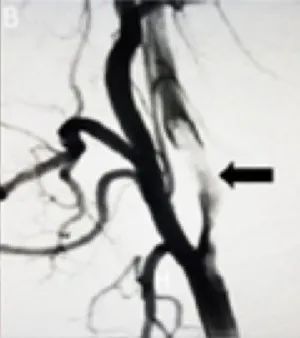

再通过导丝将大口径的ACE60再灌注导管穿过Neuron MAX。使用软尖导丝穿过颈动脉夹层段(图1B),将ACE-60导管通过导丝推进至颈内动脉远端的真性管腔。诊断性血管造影显示右侧AMCA残端闭塞(图1C)。